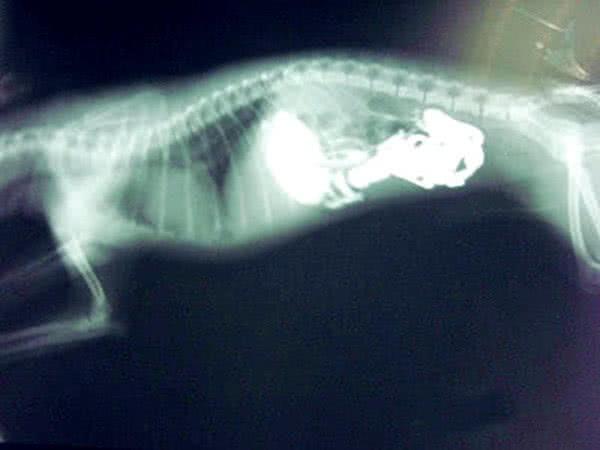

狗狗亂吃東西,痛苦的趴在地上,取出物體后主人當場臉紅